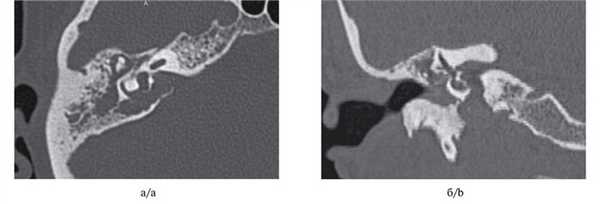

МСКТ височной кости — КТ-картина образования пирамиды правой височной кости с костно-деструктивными изменениями, правостороннего среднего отита. Образование на МСКТ височной кости отграничено сверху базальным завитком улитки и преддверием, снизу — яремной веной, медиально — твердой мозговой оболочкой задней черепной ямки, латерально — гипо- и мезотимпанумом, спереди — вертикальной частью внутренней сонной артерии, сзади — сагиттальным ПК, внутренним слуховым проходом (рис. 1). Рис. 1. МСКТ височной кости (правое ухо). КТ-картина инфралабиринтной холестеатомы пирамиды височной кости (а — аксиальная проекция, б — коронарная проекция).

Через 6 мес по результатам отомикроскопии, МСКТ височных костей, МРТ среднего уха в DWI-режиме: в сосцевидном отростке, в аттико-антральной области, в области нижней и задней граней пирамиды височной кости визуализируется обширная послеоперационная полость; в барабанном и мастоидальном сегментах послеоперационной полости пристеночно визуализируется содержимое умеренно неоднородной структуры, гетерогенного МР-сигнала в Т2 ВИ, STIR, T2 flair, изоинтенсивное в Т1 ВИ, без повышения сигнала на DWI c коэффициентом В 1000 и вычитанием на ИКД-картах (вероятно, рубцово-фиброзные изменения): данных за рецидив холестеатомы получено не было (рис. 4). Рис. 4. МР-томограмма среднего уха, выполненная в DWI- режиме.